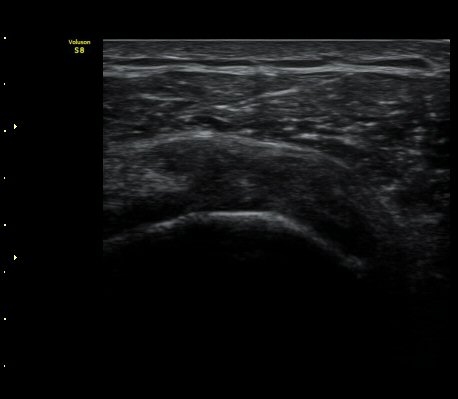

±Ø»ó°Ç Ⱦ´Ü¸é°Ë»ç½Ã ±Ø»ó°Ç ÀϺΠÀú¿¡ÄÚ ºÎÁ¾°ú ¹Ì¼¼ÇÑ °Ç ¿¬°á¼º ¼Ò½ÇÀÌ °üÂûµÊ(±×¸² 4, 5).

±×¸² 4)¿¡¼­ °üÀý¿¬°ñ°æ°è¸é ¡ÈÄ(articular interface sign)°¡ °üÂûµÊ.